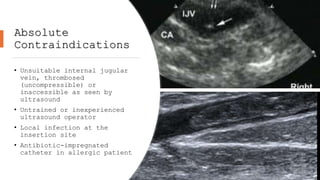

Absolute

Contraindications

• Unsuitable internal jugular

vein, thrombosed

(uncompressible) or

inaccessible as seen by

ultrasound

• Untrained or inexperienced

ultrasound operator

• Local infection at the

insertion site

• Antibiotic-impregnated

catheter in allergic patient